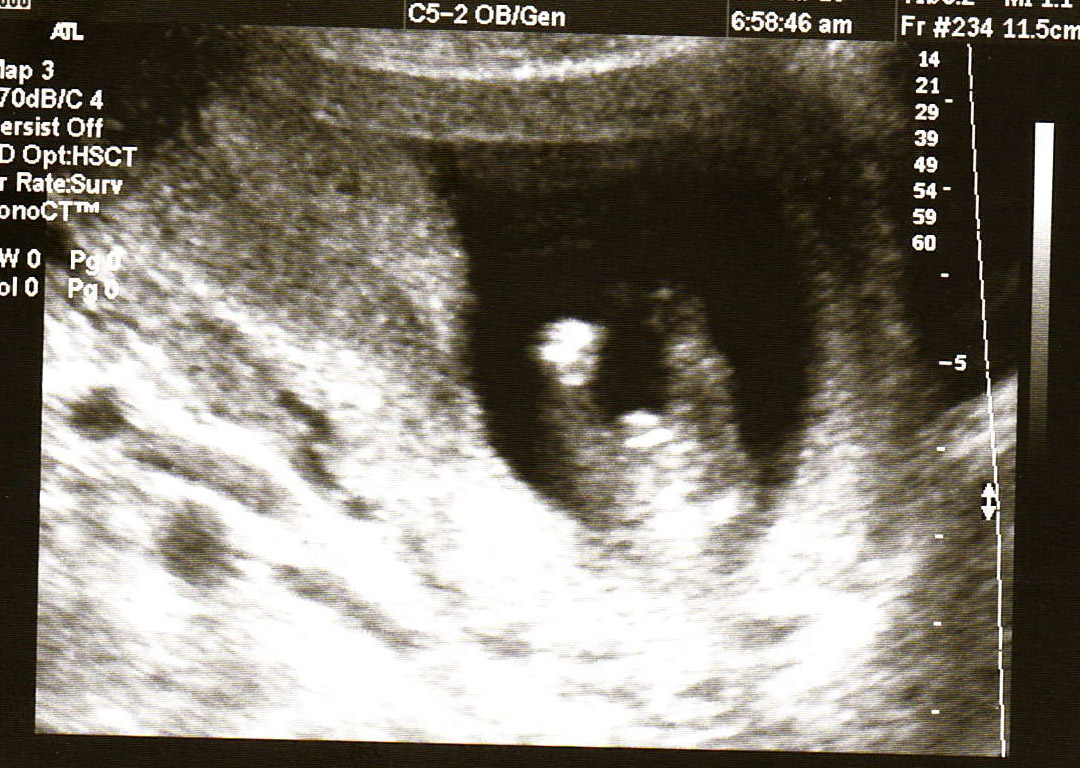

So, my wife had the ultrasound performed, we are not totally sure as to the bb's exact conception date, so we think it's between 14-16 weeks now. This is our 2nd kid. We have a boy. Looking at pictures, I can't make out what it is. I see a bulge in some, and not on others. Didn't see the 3 lines, nor did I see the turtle. What do you gals think?Attachment 27070Attachment 27069